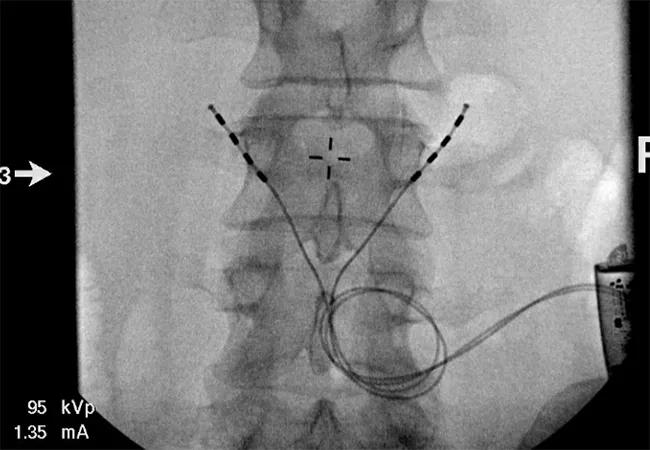

The device comprises an implanted pulse generator and two leads, which are surgically implanted under deep sedation. The ends of the leads are placed with four electrodes near the medial branch of the L2 dorsal ramus nerve where it crosses the L3 transverse processes. Tines on the ends of the leads are designed to connect to the intertransversarius muscles, safely away from the neural foramen and the dorsal root ganglion. The pulse generator can deliver stimulation between any pair of electrodes on each lead.